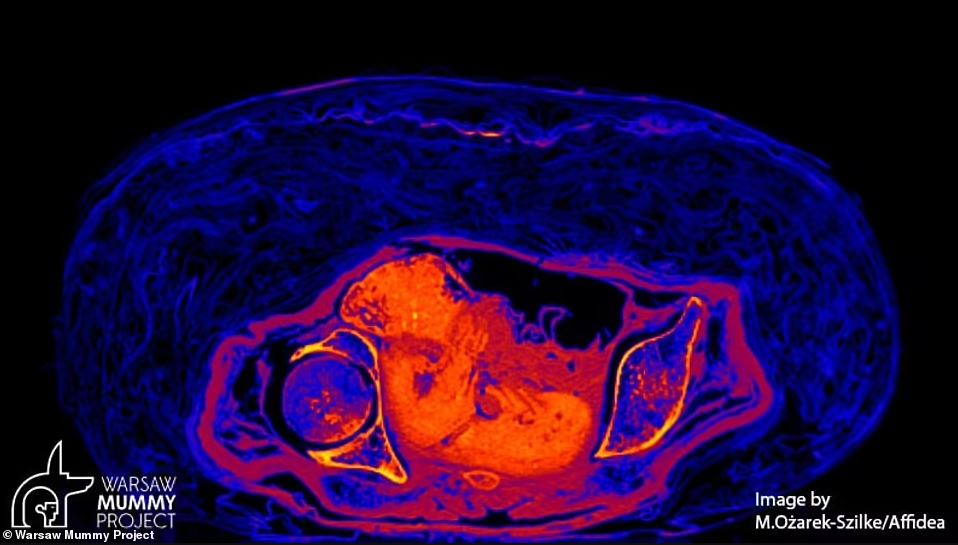

به گزارش تازهنیوز، اسکن های یک مطالعه جدید نشان می دهند که جسد ۲۰۰۰ ساله اولین مومیایی باردار مصر باستان مبتلا به سرطان بوده و احتمالاً در اثر یک نوع نادر از این بیماری در هفته ۲۸ بارداری مرده است. محققان لهستانی در حال انجام اسکن از جمجمه جسد باستانی بودند که علائم غیرعادی ای را در استخوانش کشف کردند. با توجه به اینکه، علائم مشاهده شده، مشابه آنچه در بیماران مبتلا به سرطان نازوفارنکس است، دانشمندان به این نتیجه رسیدند که این مومیایی به احتمال زیاد در اثر همان بیماری مرده است. سرطان نازوفارنکس نوع نادری از سرطان است که قسمتی از گلو را که پشت بینی را به پشت دهان وصل می کند، درگیر می کند. محققان قبلا می دانستند که این زن، ملقب به «بانوی اسرار آمیز» در هفته ۲۸ بارداری خود مرده بود، اما اکنون آنها علت مرگ او را مشخص کردهاند.

سال گذشته در معاینه ای با استفاده از تصویربرداری توموگرافی مشخص شد که این زن بین ۲۰ تا ۳۰ سال سن داشته و در هفته ۲۶ تا ۳۰ بارداری خود بوده است. به گفته نویسندگانی که در مجله علوم باستان شناسی می نویسند، جسد با دقت در پارچه ها پیچیده شده بود و با مجموعه ای غنی از تعویذها برای دیدار او در زندگی پس از مرگ همراه بود.